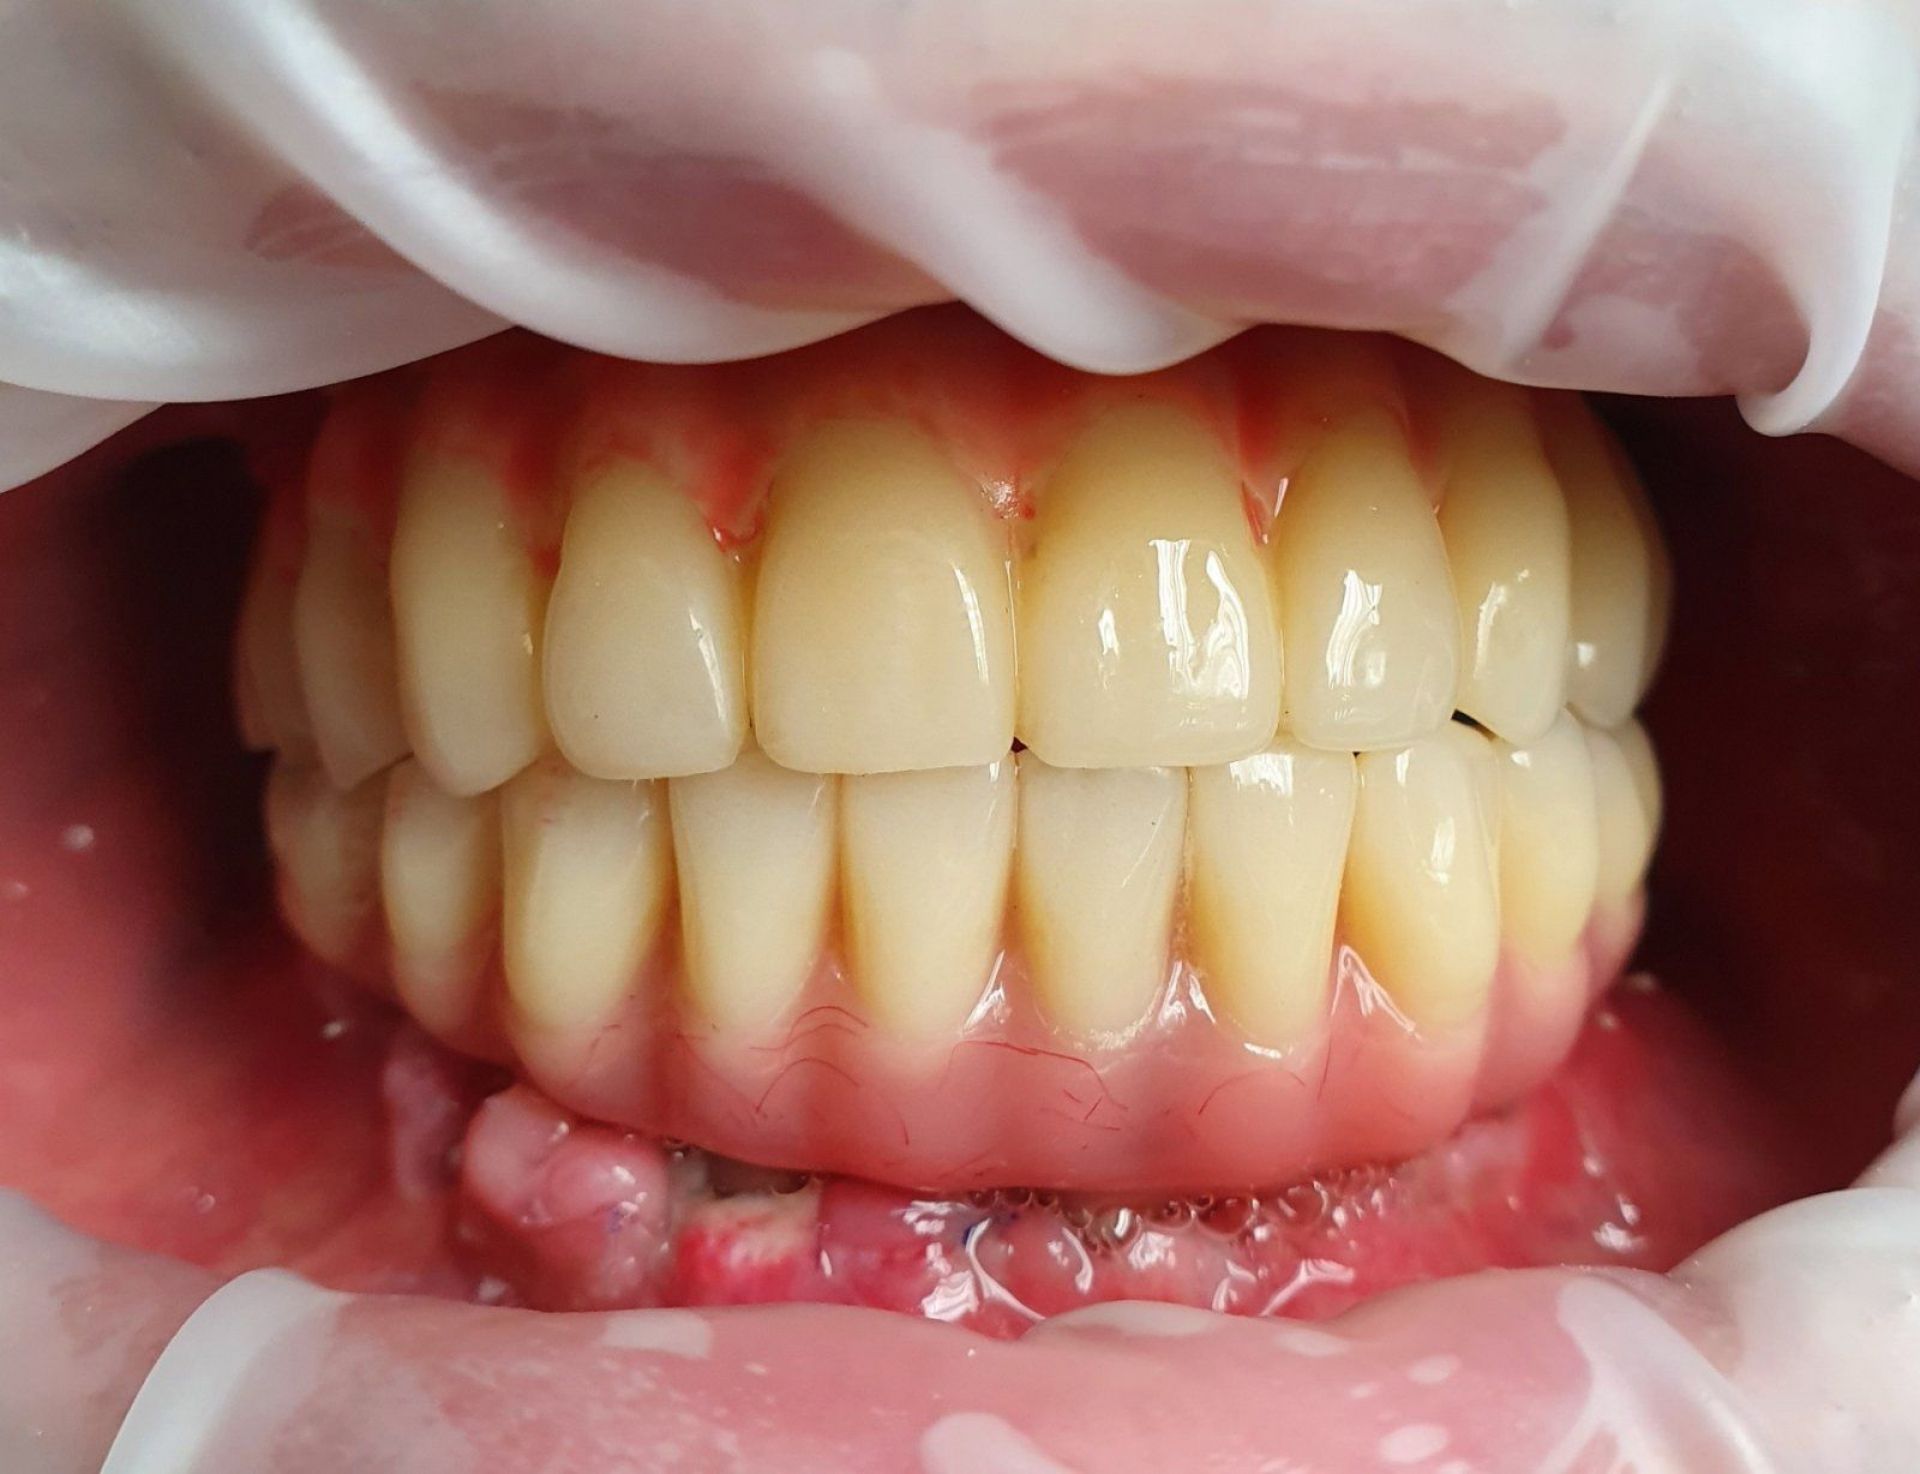

Імплант – це штучний корінь зуба, який виготовляється з титану. Він хірургічно вставляється в щелепну кістку, на ньому фіксується коронка, міст або протез. Імпланти відновлюють не лише естетику посмішки, але й функціональність зубів, даруючи Вам комфорт та впевненість.

- завершальним етапом буде встановлення постійної коронки

Якісна інноваційна імплантація приносить не тільки естетичне оформлення, а також величезну користь для організму. Вона зберігає щелепні кістки й суглоби, підтримує нормальний склад мікрофлори і шлунок отримує добре пережовану їжу.

Стоматологічна клініка VA Clinic в Хмельницькому відома своїм високим рівнем професіоналізму, застосуванням сучасних технологій та індивідуальним підходом до кожного пацієнта. Rваліфіковані лікарі забезпечать вас не лише якісною імплантацією, але й післяопераційним доглядом та підтримкою.